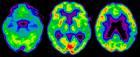

PET imaging produces a three-dimensional image, or picture, of functional processes in the body, such as brain activity, and is a highly accurate and effective method of diagnosing disease and managing patient therapy. MDS Nordion’s new facility will provide timely supply of Glucotrace to hospitals throughout Belgium, France, The Netherlands, Luxembourg and Germany.